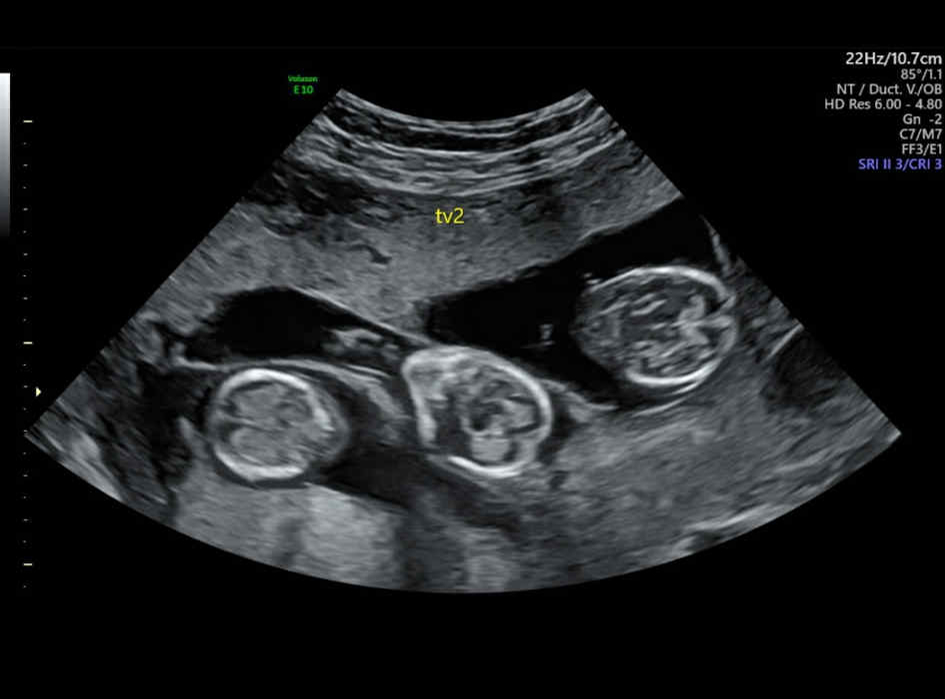

„V 50 rokoch som porodila trojčatá po tom, čo mi povedali, že naša šanca je len 5 %,“ hovorí žena, ktorá bola predtým zdravotnou sestrou. Marie a jej manžel už mali štyroch spoločných synov – 31-ročného Sebastiana, 19-ročného Jespera, 8-ročného Lea a 3-ročného Louieho. Rozhodli sa však, že by si radi zaobstarali ešte jedno dieťa. Hoci im lekári odporúčali znížiť počet embryí kvôli rizikám spojeným s trojčatami, Marie to odmietla.

„Počas prechádzajúcich tehotenstiev som nemala žiadne problémy a zakaždým som otehotnela rýchlo. Napriek tomu sme si vzhľadom na môj vek nemysleli, že tentoraz to pôjde na prvýkrát. Preto sme nechali vložiť hneď tri embryá, aby sme maximalizovali šance. Lekári hovorili, že existuje len 5 % šanca, že sa uchytia, ale napokon sa to podarilo všetkým trom. Bola som taká šokovaná a šťastná. Bol to fantastický darček,“ rozplýva sa Švédka.